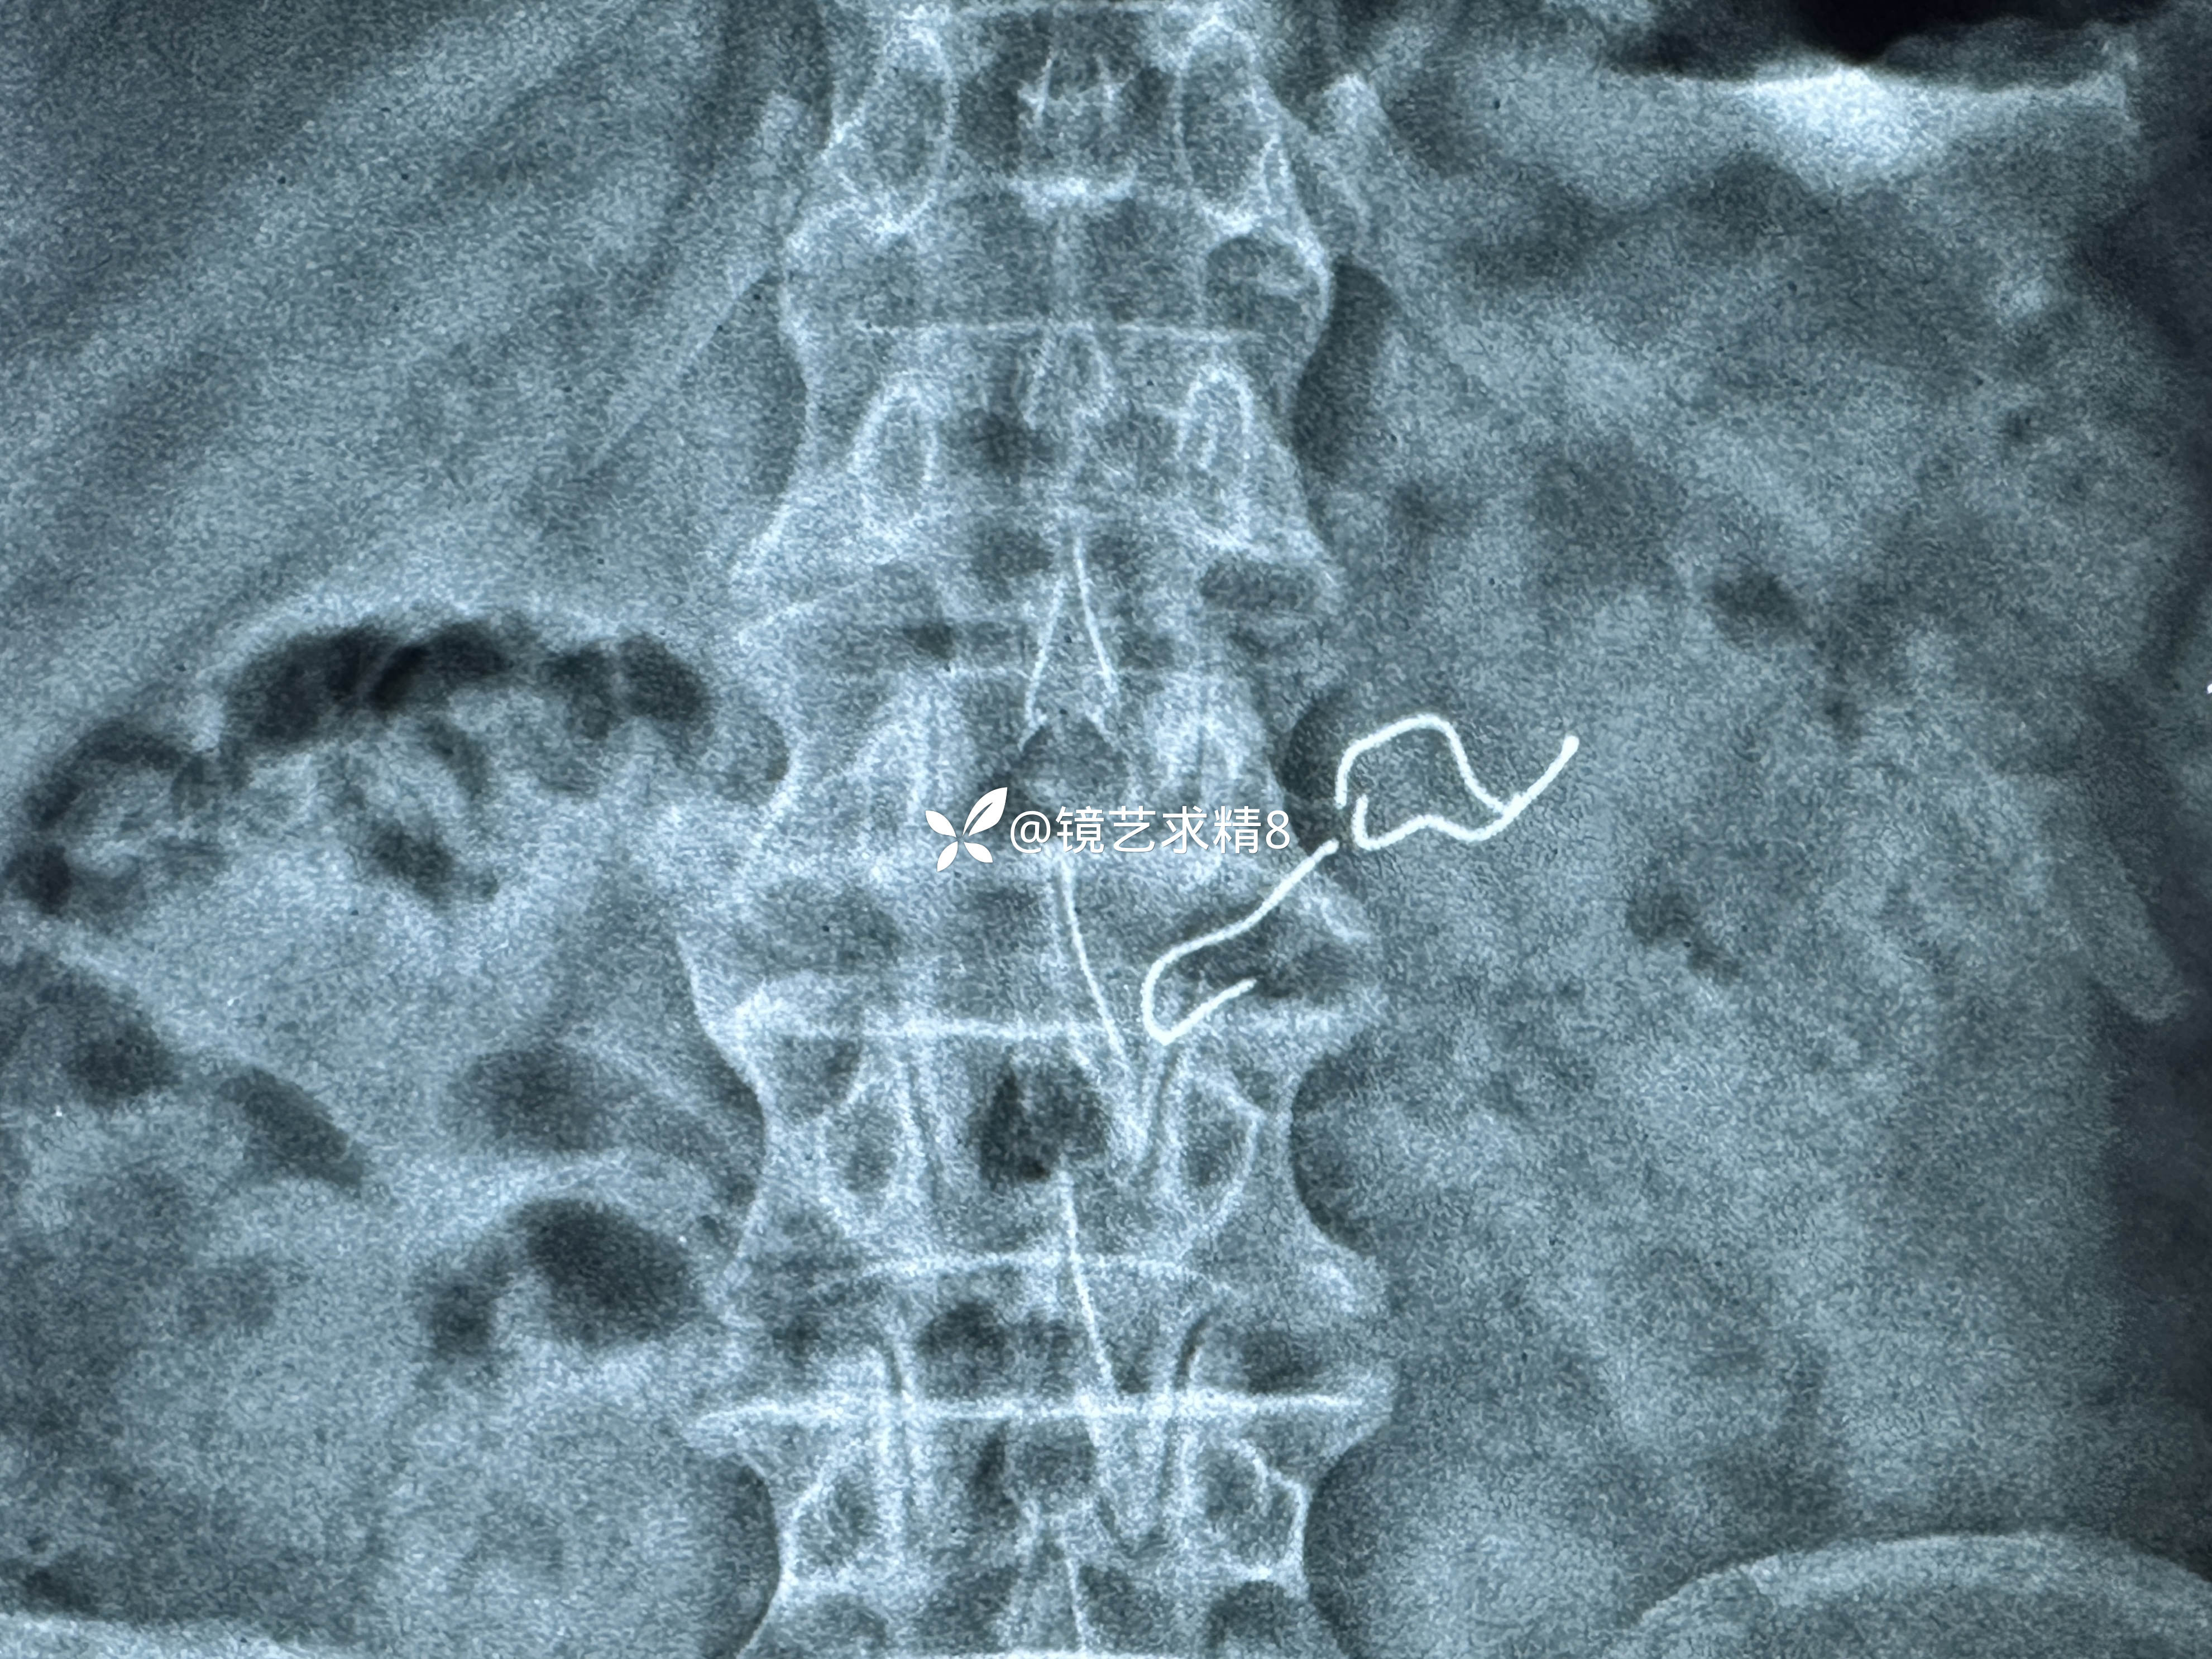

患者 老年 男性,因不慎吞入假牙,外院X光片所见假牙约5cm,两端有带钩钢丝。

从X光片看,为确保取出过程中钢丝钩损伤消化道黏膜,计划将异物收入避孕套内可以达到预防消化道黏膜损伤这一目的,特备好避孕套。